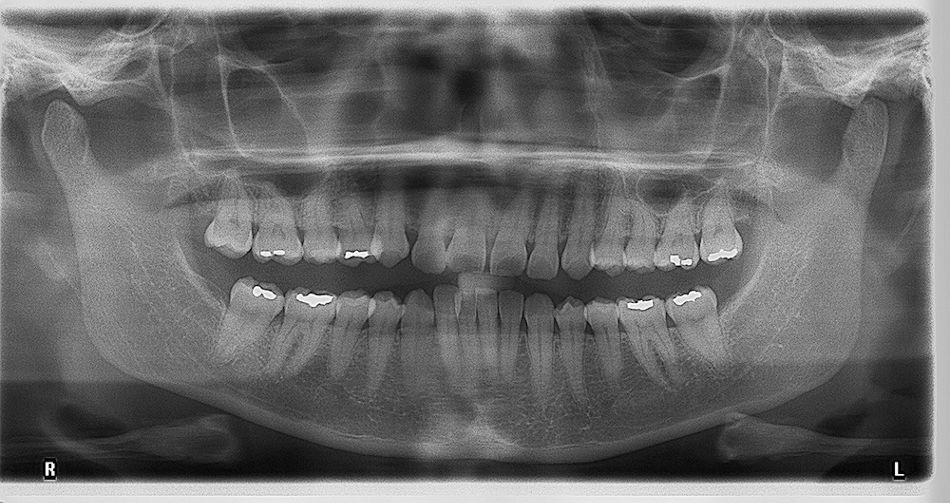

Die FRS-Auswertung ergab eine distal-basale Kieferrelation nach WITS (2,6mm) bei tendenzieller maxillärer Prognathie (SNA 86,5°). Aus der dentalen Analyse des FRS ging eine deutliche Anteinklination der Oberkieferinzisivi (IOK-NL 126,5°) und eine manifeste Anteinklination der Unterkieferinzisivi (IUK-ML 103,6°) bei stark verkleinertem Interinzisalwinkel (IOK-IUK 112,3°) hervor. Die vertikalen Parameter ergaben einen brachiofazialen Gesichtsschädelaufbau. Die Auswertung des OPG zeigte eine adulte Dentition mit fehlenden dritten Molaren. Ausserdem war eine extreme Mesialkrümmung der Wurzel 25 erkennbar. Es zeigte sich ein moderater generalisierter horizontaler Knochenabbau des Limbus alveolaris im Ober- und Unterkiefer von ca. 15%.